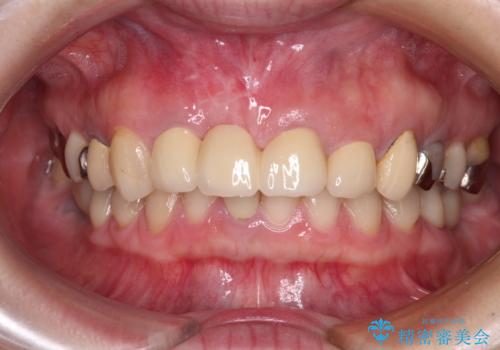

歯肉移植終了後、オールセラミックブリッジにて補綴することとしました。

歯肉移植により歯肉ラインや歯の形態を整えることができ、ブリッジによる補綴としたことで舞えば全体の色調を整えることができました。